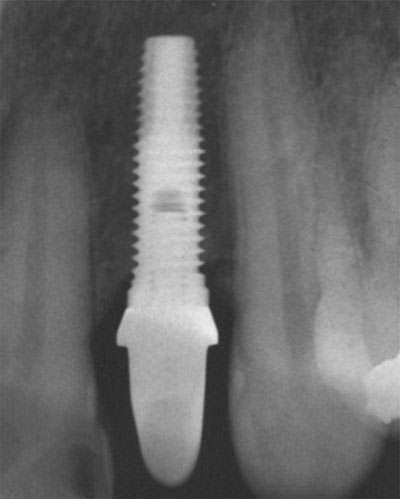

Fig. 4

Radiografía periapical de implante Restore® ubicado en zona de pieza 22.

Seguidamente se realizó una entrevista al paciente con la finalidad de determinar si se presentó alguna complicación relacionada al implante. Después, se realizó una evaluación clínica con registro de la presencia o ausencia de alguna patología o complicación actual. El registro se realizó en una ficha en la que se incluyeron los siguientes parámetros clínicos propuestos por Albrektsson y colaboradores 9: ubicación del implante, ausencia de movilidad del implante determinada por la aplicación lateral de presión con dos instrumentos a ambos lados del implante, ausencia de dolor, parestesia y de alguna infección atribuible al implante. Figura 1. Además se tomaron radiografías periapicales utilizando la técnica paralela, debiendo aparecer nítidamente las roscas del implante de tal manera que permita examinar la unión con el tejido óseo en el fondo de la rosca. Además, se modificó un posicionador de películas radiográficas marca Maquira® (Maringá, Paraná, Brasil) con un dispositivo de acrílico individualizado para cada implante, de modo que posteriormente pueda repetirse la toma radiográfica en la misma posición, permitiendo realizar un seguimiento con mediciones más exactas de la pérdida ósea y que estas puedan ser comparadas a futuro. Figuras 2 y 3. Se utilizaron películas dentales para técnica periapical Insight® (Kodak Dental Systems, Rochester, New York, USA), tamaño 31x41mm y sensibilidad "D". El equipo radiográfico utilizado fue Elitys® (Trophy Radiologie, Beaubourg Marne La Vallee, Francia); y las tomas radiográficas fueron a 70Kv y 8mA. Además, se utilizó un procesador de películas automático GXP® (Gendex Dental Systems, Des Plaines, IL, USA); realizándose el procesado a 36º de temperatura y con un tiempo programado de 4 minutos. Una vez obtenida la placa con la imagen radiográfica deseada, se evaluó la presencia de alguna zona radiolúcida alrededor del implante, que nos pueda indicar alguna alteración del proceso de oseointegración, además de medir la pérdida ósea marginal tanto en el lado mesial como en distal. La pérdida ósea se determinó midiendo la distancia desde la base de la plataforma del implante hasta el primer punto de contacto hueso-implante. Figuras 4 y 5. Las mediciones en todos los casos fueron realizadas por un mismo examinador calibrado. Las mediciones se realizaron mediante la utilización de un Calibrador Pie de Rey Digital Ultra Tech®, Fraction+ (General Tools & Instruments, New York, USA), un negatoscopio con un lente de aumento de 1.5X y fueron realizadas en una habitación oscura. Se consideró como parámetro de éxito para los implantes, una pérdida ósea marginal de 1,5mm durante el primer año después de su colocación y en adelante 0,2mm por año 9.